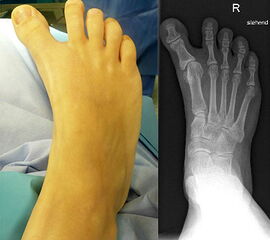

Klinisches Erscheinungsbild eines Hallux varus (eigenes Bildmaterial)

Abbildung 1

Bei einer geringgradigen Ausprägung eines Hallux varus (bis ca. 10° negativer Hallux-valgus-Winkel) sind die Betroffenen selten beeinträchtigt, in der Regel bedarf es keiner Therapie. Die Korrektur durch den Druck der Zehenkappe im Schuh ist meist bereits ausreichend.

Bei zunehmender Fehlstellung klagen die Patienten über Druckbeschwerden im Schuh, insbesondere am Endglied innenseitig oder über dem IP-Gelenk der Großzehe sowie über bewegungsabhängige Schmerzen im 1. MTP-Gelenk. Häufig sind die Betroffenen auch kosmetisch unzufrieden (Janis et al., 1975).